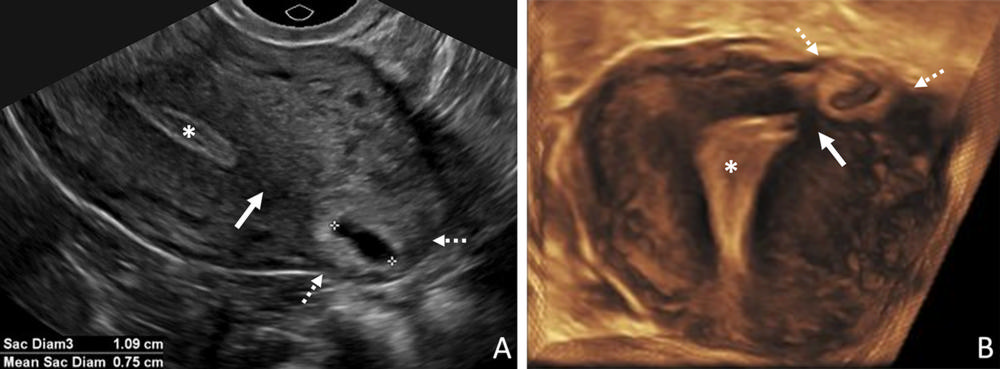

Figure 6. Normal intrauterine pregnancy (IUP) variant: eccentrically located gestational sac (GS) completely surrounded by endometrium. (A) Transvaginal transverse grayscale and (B) coronal reformatted three-dimensional US image in a 36-year-old pregnant patient shows an off-midline (leftward) GS (arrow) at 5 weeks 4 days with yolk sac and embryo. The GS is completely surrounded by endometrium and may be reported as an IUP without further description. If desired, the user may describe as an eccentrically located GS completely surrounded by endometrium but should conclude as an IUP to obviate concern for an interstitial ectopic pregnancy. The terms ‘angular’ or ‘cornual pregnancy’ should be avoided. Coronal reformatted three-dimensional US may help confirm a GS is located within endometrium, as demonstrated in this case.